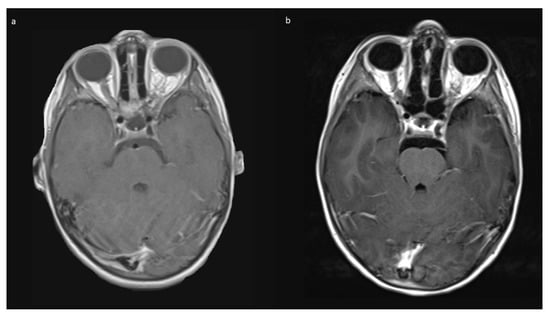

Indications for surgery were blindness/non-serviceable vision of the affected eye, disfiguring exophthalmos, pain, and documented tumor growth. A combination of factors was often present. All preoperative MRIs showed contrast-enhancing tumor growth from the orbit into the optic canal, and in 8/10, further intradural tumor extension affecting the ipsilateral optic nerve but not the optic chiasm (Figure 1).

No intraoperative or immediate post-operative complications were observed, and patients were usually discharged with orbital swelling and not yet or returning levator palpebra function. In the follow-up, two children developed enophthalmos, one with minimal levels and one with moderate ptosis due to levator palpebra muscle weakness. Both children had received radiotherapy prior to surgery. The other eight (80%) children had no obvious oculomotor or cosmetic deficit of eye position and movement. Figure 4 shows an example of resolution of exophthalmos on MRI after tumor removal.

3.6. Follow-Up

The mean follow up was 42.0 (range 2–74) months in Group A, and 15 months in Group B. Patients received MRIs at 3 months post-surgery, then in cases of no residual tumor, every 6 to 12 months, depending on previous tumor growth velocity for up to 5 years. The case with unintended STR (No 1, Table 1) showed tumor progression in imaging and was subsequently treated with chemotherapy. No further growth was observed thereafter. In the two cases from Group B, there was stability of the intended residual optic nerve within the optic canal and no signs of tumor recurrence originating from there. In two of the four cases with NF1, a very small contralateral optic nerve glioma (MRI signal intensity changes and minimal contrast uptake, but no significant tumor extension) was known prior to surgery. Since in both children, no impairment of vision (visus 0.8 and 1.0) existed, this tumor manifestation was only observed in accordance with guidelines that asymptomatic tumors do not deserve treatment. An exemplary MR image set is provided in Figure 7.

Figure 1. Exemplary MR-imaging of a 3-year-old male (a) preoperatively, (b) 1 month postoperatively, and (c) 2 years postoperatively.

Figure 4. Exemplary MR imaging follow-up of a child with (a) preoperative exophthalmos on the left side and (b) postoperative normal eye position.